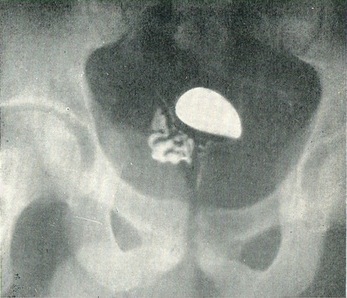

У нормі міхур, наповнений контрастним речовиною, має округлу форму; щільність контрастною середовища однакова. Контури міхура рівні (рис. 43).

Рис. 43. Нормальна цистограмма.